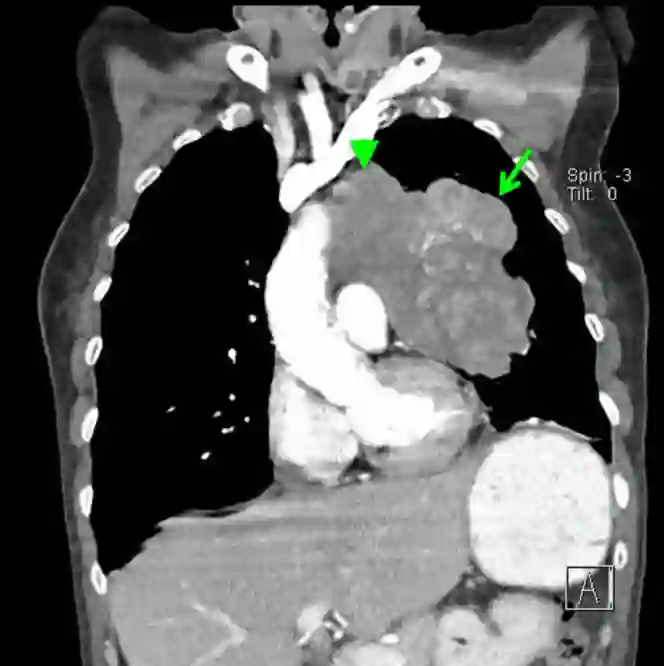

SCLC具有典型影像学表现:肺门增大、纵膈淋巴结受累(图1),常伴转移,多累及肝脏、肾上腺、骨和/脑。SCLC有时在肺内损害很小甚至难以鉴别,但受累淋巴结却很大,当然不是所有SCLC都有典型影像学表现,最终诊断需要组织学证实,可以是细针活检、活检或切除。SCLC是高级别神经内分泌肿瘤,特征是小细胞、胞浆少、核质细、染色质疏松、无显著核仁,大部分SCLC至少表达一种神经内分泌标志,但神经内分泌标志检测并非诊断所必需。

图1 胸部CT冠状位,SLLC累及左上肺叶(绿色长箭头)并延伸入纵膈(绿色短箭头)